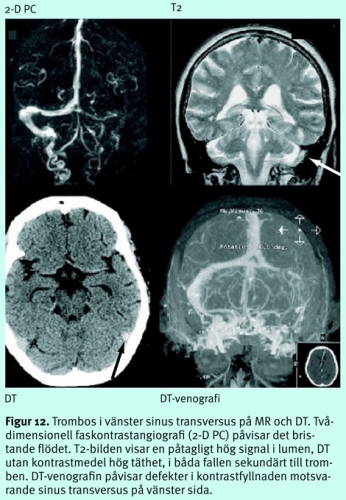

De snabba framstegen vad gäller framför allt MR-diagnostiken kring durala vensinus och hjärnans centrala vensystem har, tillsammans med mer differentierade behandlingsrutiner, bidragit till att prognosen för patienter med sinustrombos och besläktade tillstånd förbättrats betydligt. För att påvisa venocklusionen används antingen noninvasiv MR-teknik känslig för långsamma flöden, där skillnader i protonspinnens fas mellan rörliga protoner i venerna och statiska spinn i vävnad utnyttjas (faskontrastbilder, PC), eller höga signaler från osaturerade protoner som flödar in i det avbildade snittet (inflödesangiografi, TOF), alternativt MR-angiografi under intravenös kontrastinjektion (CE-MRV).

Inte sällan får flera tekniker kombineras för att få en konklusiv tolkning. Konventionella MR-bilder bidrar här, eftersom MR dels har god känslighet för sekundära förändringar som ödem eller hemorragiska lesioner orsakade av stas, dels ibland visualiserar själva trombmassorna eller abnorma signaler i kortikala vener (Figur 12). Vid DT utan kontrastmedel är det jämförelsevis svårare att detektera tromber (täthet högre än vad som svarar mot den normala hematokriten) och påvisa ödem. DT-venografi under kontrastinjektion ger en bättre diagnostisk säkerhet än MR, eftersom metoden besväras av färre tekniska svårigheter och fallgropar än MR. DT kombinerad med DT-venografi kan därför komma att etablera sig som första linjens diagnostik vid misstänkt sinustrombos, särskilt som tillgången till MR under jourtid på många håll är dålig.

Patienter med sjunkande medvetandegrad, eventuellt svårkontrollerade kramper och påvisad svår sinustrombos kan behöva diskuteras för akut interventionell behandling, med kateterangiografi och -venografi, följd av trombektomi och/eller intravaskulär trombolys.